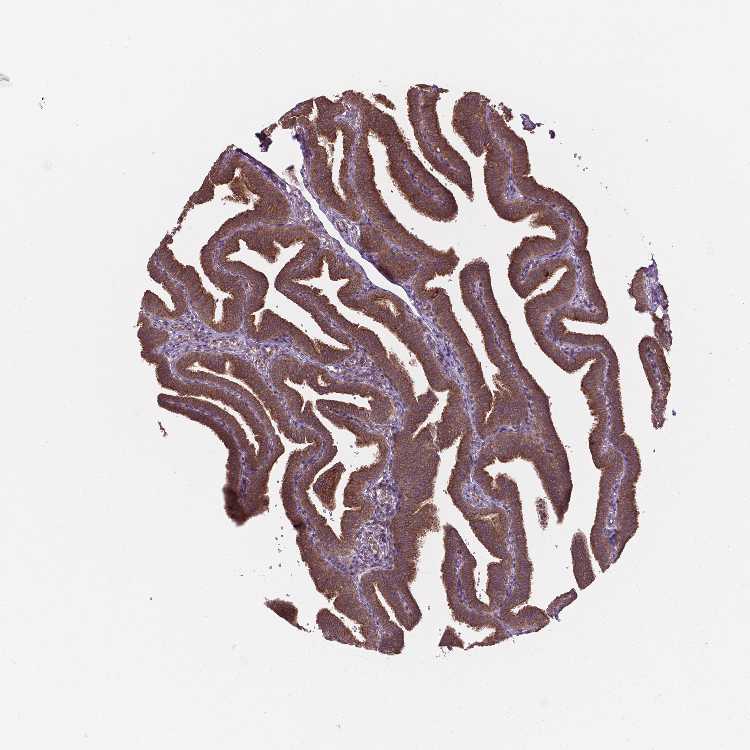

FALLOPIAN TUBE - Antibody stainingi

Antibody staining in the annotated cell types in the current human tissue is reported as not detected, low, medium, or high, based on conventional immunohistochemistry profiling in selected tissues. This score is based on the combination of the staining intensity and fraction of stained cells.

Each image is clickable and will lead to virtual microscopy that enables deeper exploration of all samples and also displays staining intensity scores, fraction scores and subcellular localization as well as patient and tissue information for each sample.

Antibody HPA066872

Glandular cells Medium